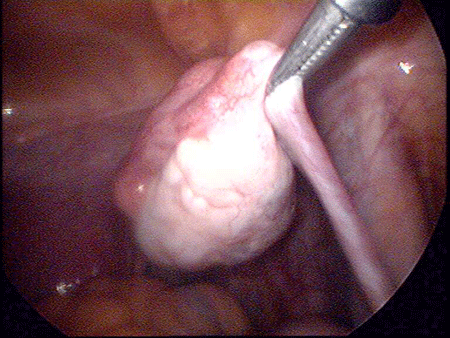

先天性无阴道手术

极少数先天性无阴道病人伴有正常子宫,进入青春期月经初嘲时下腹痛,以后出现周期性腹痛。阴道再造术后能进行性生活,并有可能正常生育。

对于先天性无阴道的“石女”可用压迫扩张法和阴道成形术矫治。所谓压迫扩张法,就是在相当于阴道外口的浅窝处,用光滑的钝头木制圆棒施加机械性压力,每日压迫2次,每次20分钟,约经3个月左右,浅窝可达7-8厘米深度。如此压迫扩张出来的阴道,基本可满足性生活的需要。